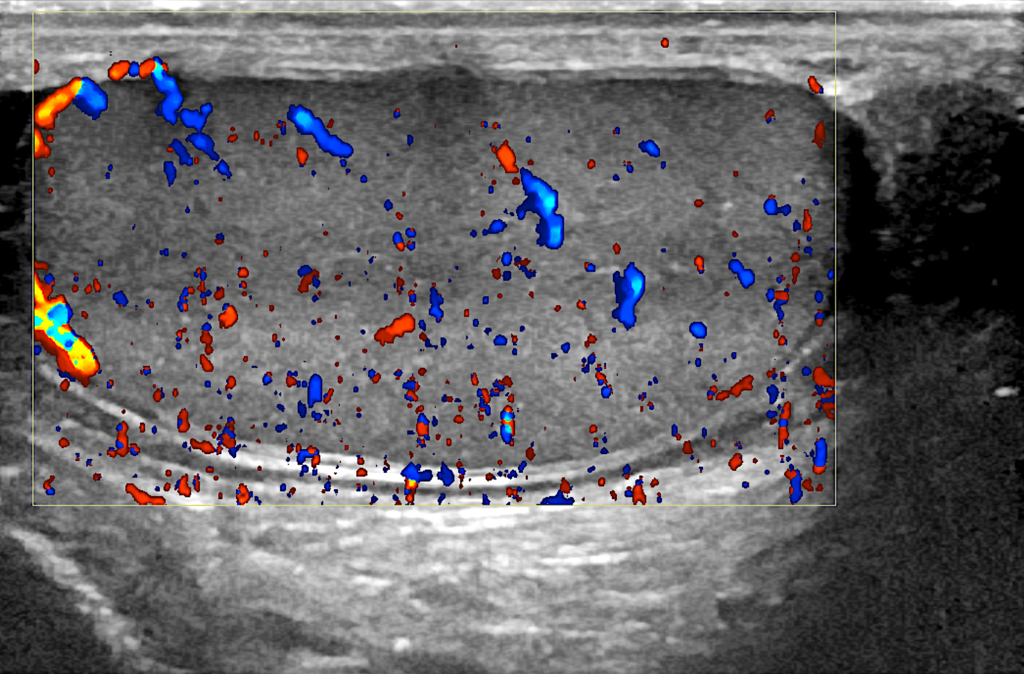

Για τους λόγους αυτούς, μόνο ωφέλιμη αποδεικνύεται η απεικόνιση της αιμάτωσης των όρχεων μέσω της διενέργειας έγχρωμου υπερηχογραφήματος των όρχεων (triplex οσχέου), εξέταση που αναδεικνύει τόσο την αρτηριακή όσο και την φλεβική αιματική ροή των όρχεων και της επιδιδυμίδας, ενώ ταυτόχρονα μπορεί να αποκαλύψει ενδεχόμενη διαταραχή στην αιμάτωσή τους, από καταστάσεις όπως είναι η κιρσοκήλη.

Triplex οσχέου σε άνδρα ασθενή μας με αριστερή ευμεγέθη οσχεοκήλη, το οποίο αναδεικνύει ομαλή αιματική ροή προς τον αριστερό όρχι.